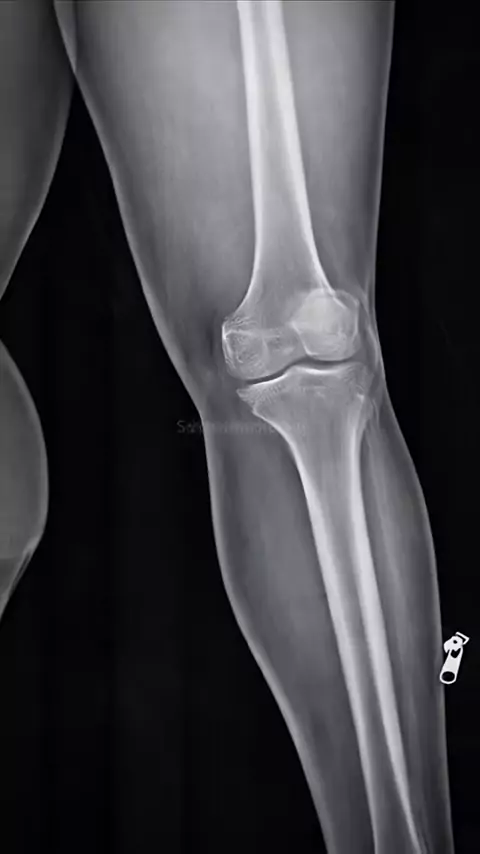

#asmr #bone #xray #radiologia